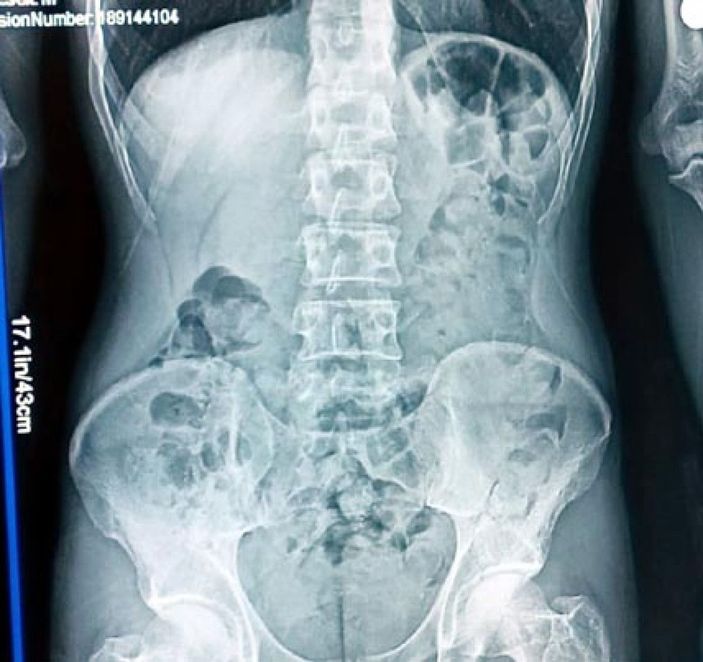

Şefik B. midesinde kapsül halinde uyuşturucu madde olduğunu itiraf edince, hastaneye götürülerek röntgeni çekildi.

Röntgende, Şefik B.’nin midesindeki kapsüller görüldü. Doğal yöntemle çıkan 48 parça halindeki 542 gram eroine el konuldu.